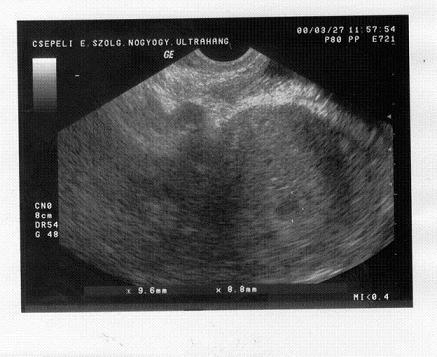

Tegnapi két kép:

Kép

Adatok pedig:

a petezsák 47mm

a baba 19mm

Óriás bébi :lol: